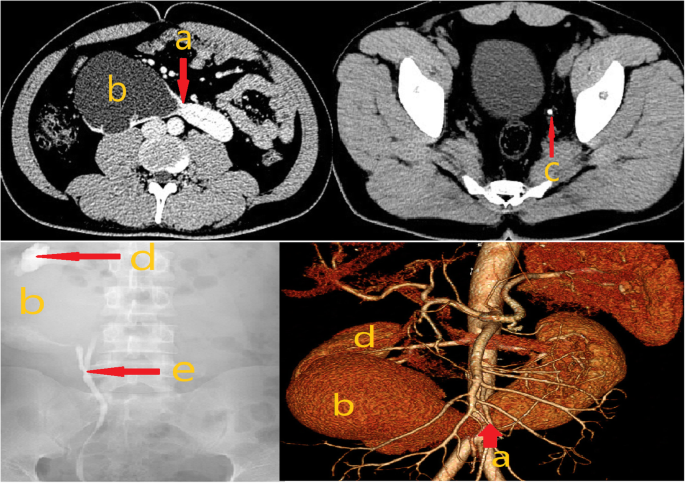

On admission, abdominal enhanced computed tomography (CT) combined with CT ureterography (CTU) showed the following: bilateral lower pole fusion; a low-density region (83 × 85 × 114 mm) in the right kidney during the arterial phase without entrance of the contrast agent in excretory phase and a left ureteral calculus with a 2.9-mm diameter. The multiple diagnoses of HSK with a right renal cyst and left ureteral calculus were suspected. (Fig. 1).

Considering the abnormal shape of renal cyst, however, we thought that the possibility of right hydronephrosis could not be eliminated. Therefore, a retrograde urography study was conducted, which showed a duplicated renal pelvis and ureters with severe hydronephrosis in the right lower renal pelvis (Fig. 1). Furthermore, results of renal imaging showed that the right lower kidney had no blood supply, whereas the right upper kidney had a normal blood supply; the glomerular filtration rates (GFRs) were calculated to be 0 mL/min and 23.7 mL/min, respectively. No other abnormalities were evident on other examinations. Based on these results, the diagnosis was confirmed as HSK accompanying a right duplicated kidney, severe hydronephrosis with a nonfunctioning right lower kidney and a left ureteral calculus.